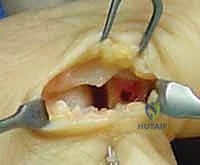

تعتمد استراتيجية العلاج التي يتبناها الأستاذ الدكتور محمد هطيف على درجة الإصابة، عمر المريض، مستوى نشاطه (رياضي محترف مقابل شخص عادي)، والوقت المنقضي منذ الإصابة.

الخيارات العلاجية: من العلاج التحفظي إلى الجراحة المتقدمة

| الدرجة الثالثة (Grade III) | تمزق كامل للرباط (انفصال تام). | ألم مبرح (قد يقل لاحقاً بسبب قطع الأعصاب الموضعية)، تورم شديد، كدمات واسعة، فقدان كبير لقوة القبضة. | عدم استقرار واضح (رخاوة شديدة). غياب نقطة التوقف عند اختبار الإجهاد. احتمال كبير لوجود "آفة ستينر". | تدخل جراحي حتمي ومبكر: لإعادة ربط الرباط بالعظم واستعادة استقرار المفصل، يليه تأهيل مكثف. |